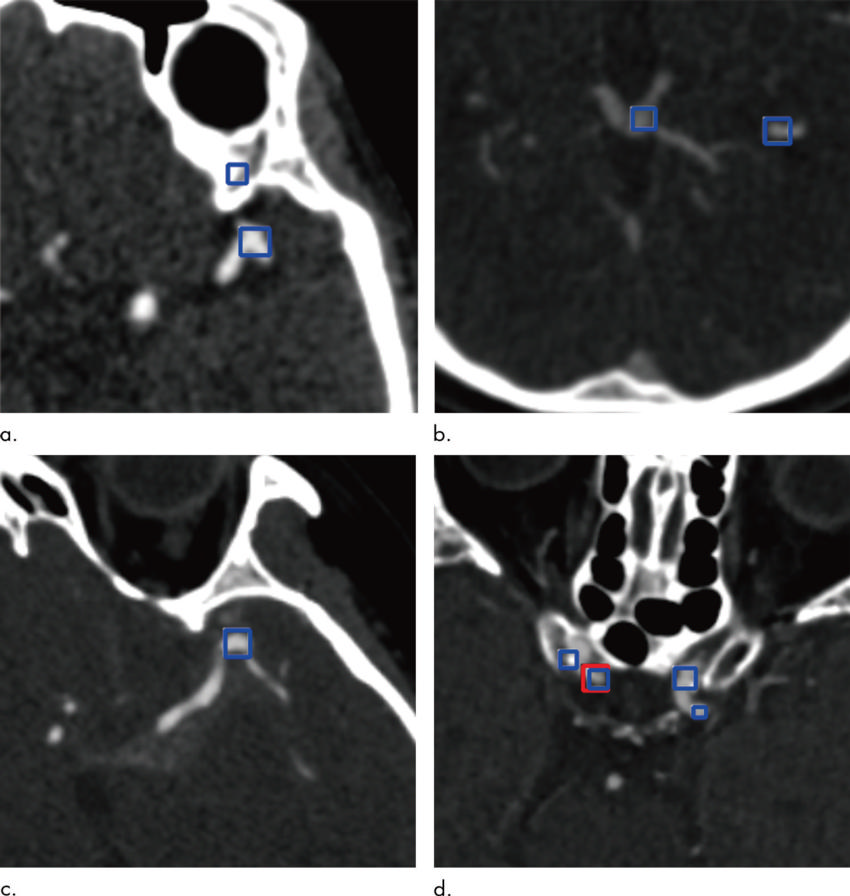

Figure 3. Images show examples of false-positive aneurysms, including (a) bony structures and vessel bifurcation, (b) veins, (c) vessel curvatures, and (d) calcified plaques. Red box (d) indicates aneurysms annotated by radiologists, and the blue boxes indicate aneurysm candidates provided by the algorithm.